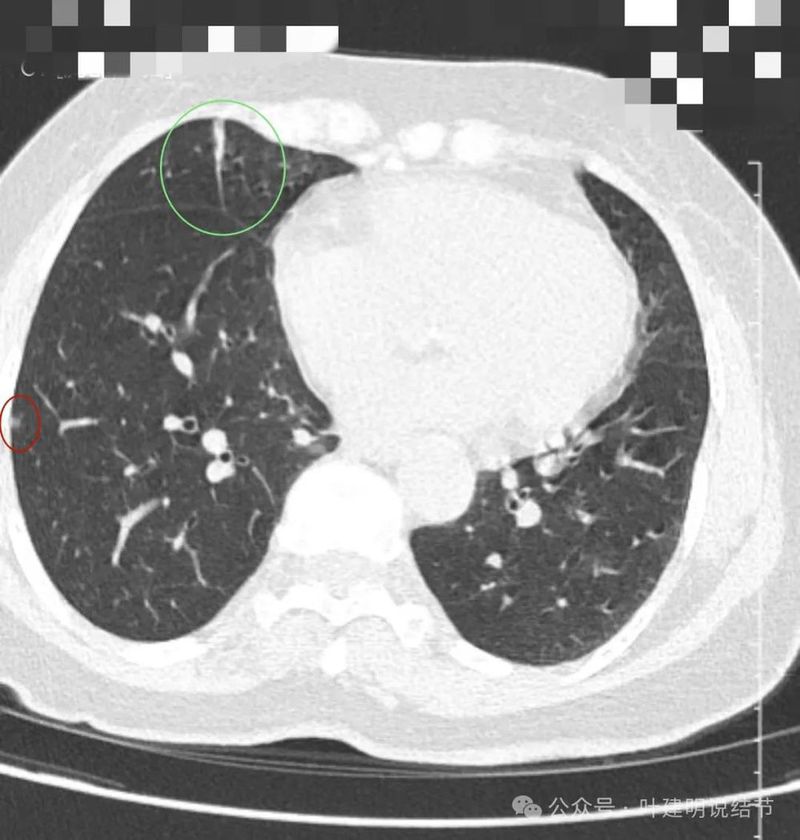

右下叶囊腔型病灶,囊壁较薄,内部有分隔,囊腔型肺癌不能完全除外,但肯定要先随访起。

右下另处囊腔灶,灶内有血管穿过,整体小且囊壁薄,再观察下。